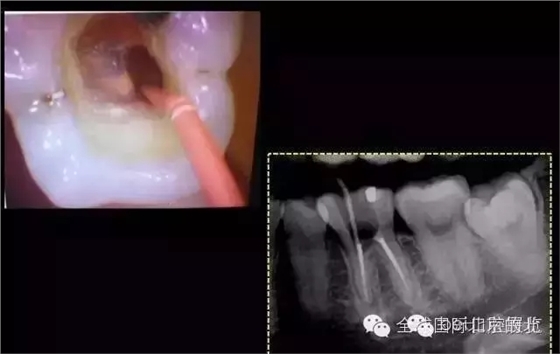

本來是給患者上橡皮障的,但是患者很不舒服,最后還是沒用,所以盡量沖洗到位+EDTA,DB,DL,很順利疏通和預備,MB,ML,也同時S3預備完成,F104錐度試尖,但是覺得可能還有根管存在。

DB,DL.根管充填完成,樹脂封閉根管口,繼續(xù)探索未知的近中隱藏根管,所以決定拍1/4 CBCT確認MB存在, 其實預備的是MM和ML,